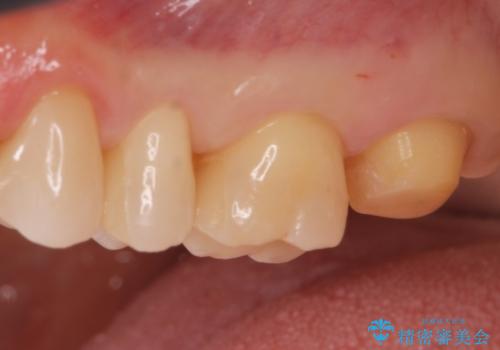

- 銀歯を無くしたいとの事で来院。

拡大鏡下でメタルを除去し虫歯がないことを確認してから白い詰め物、被せ物で治療を行いました。

適合の良い詰め物、被せ物が入りました。